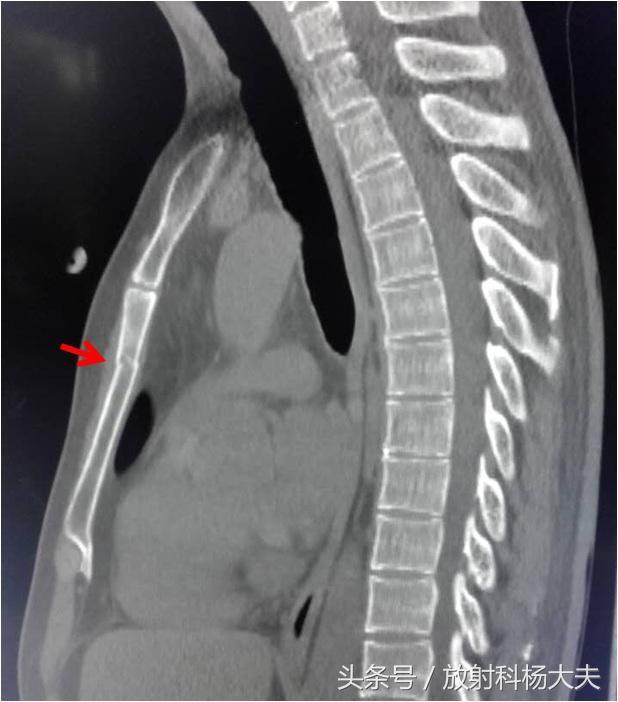

先看看病人的CT吧,箭头所示是胸骨,骨质断裂了,没错,是胸骨骨折。

这骨折怎么来的?经询问,原来是女主人公在男朋友开车过程中,玩心兴起,将身子探出天窗外,感受迎面春风拂面的美好,顺道摆摆酷,结果前面马路上突然乱入一条狗狗,一个急刹车,胸部撞在天窗边缘上。据描述,女主人公当时就听到“咔嚓一声”,急忙来到医院。三分钟的潇洒后,换来了胸骨骨头的断裂,不小的金钱和时间花费。